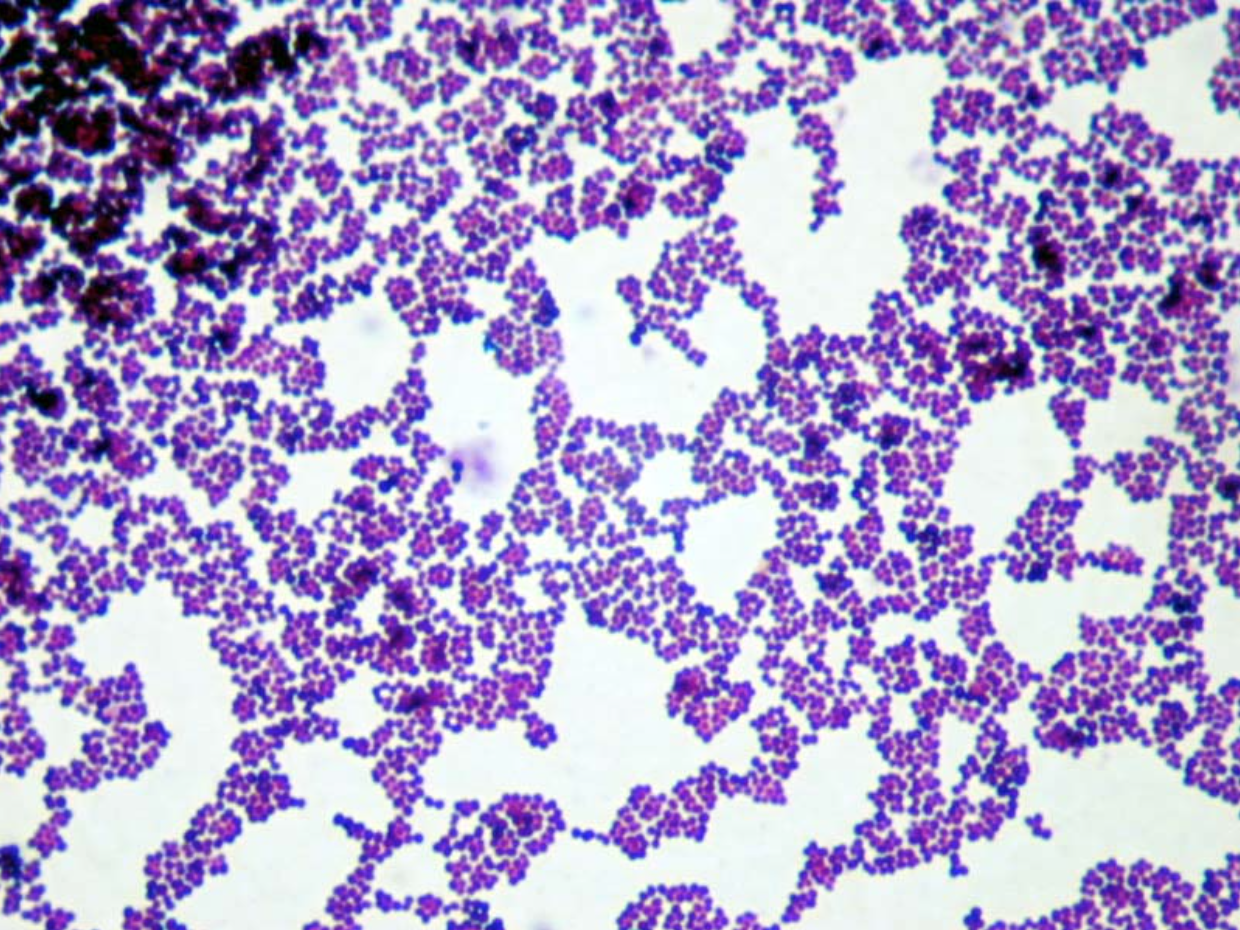

Staphylococcus aureus в мазке

Staphylococcus aureus в мазке 118 фото